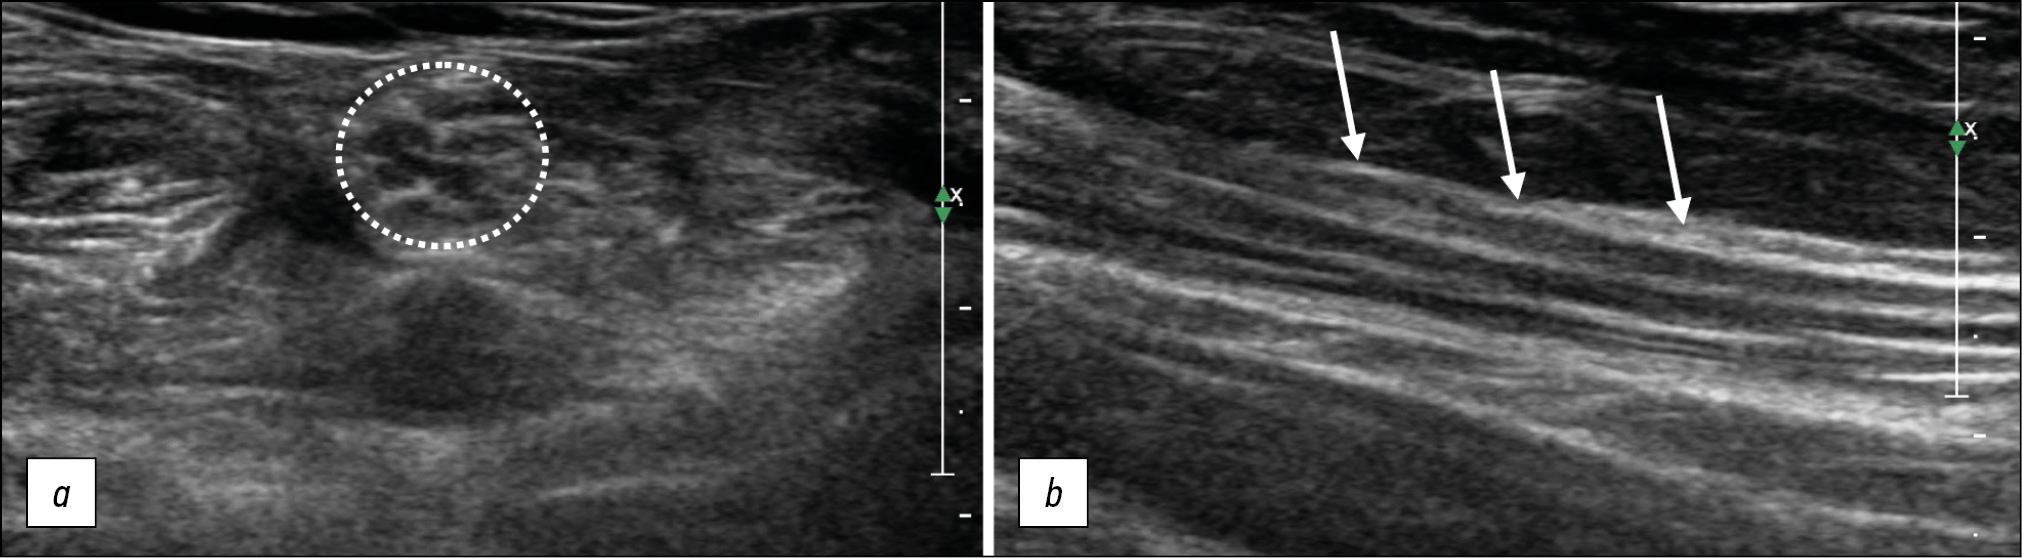

US is used to assess the volume (thickness) of muscle tissue for any muscle groups or individual muscles, to identify fibrotic changes, denervation processes (Fig. 3), as well as to determine the presence of spontaneous muscle contractions.

Fig. 3. Denervation changes in the quadriceps femoris muscle, longitudinal sonogram. (a) unchanged muscle, (b) denervated muscle: the muscle volume is reduced in volumewith increased echogenicity, and no differentiation of fibers.